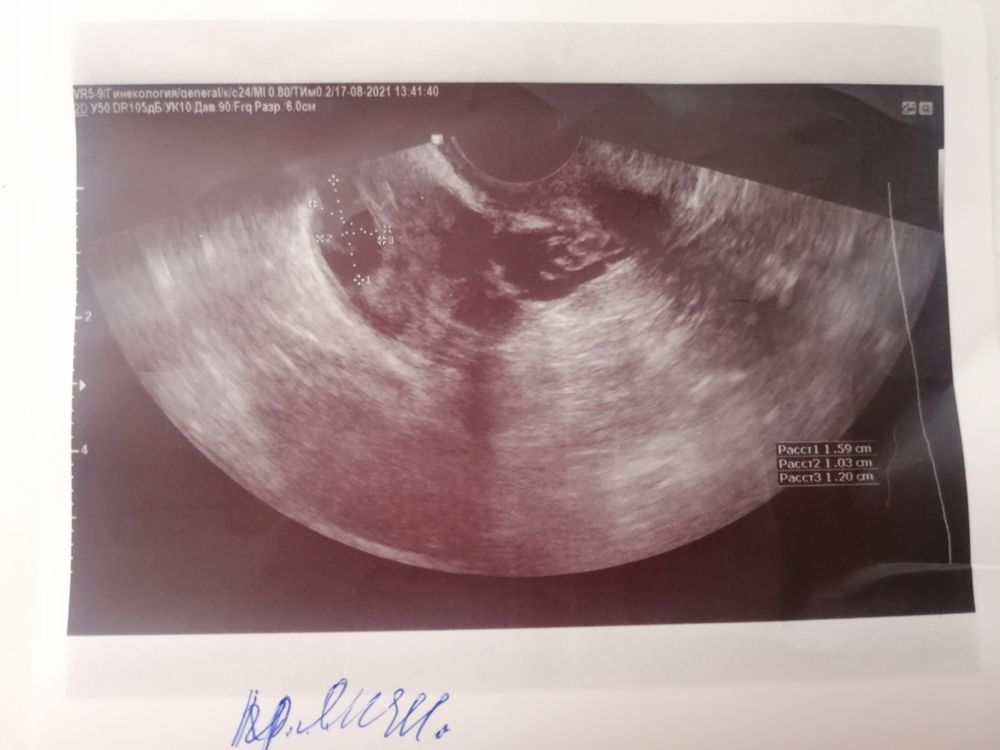

Здравствуйте. Сегодня сходила на фолликулометрию. Врач сказала 19 мм фолликул и дала фото, заключение не брала у неё. Уже потом посмотрела фото и поняла, что там максимальный размер 15.9мм. Может дф рассчитывают по формуле? Спасибо